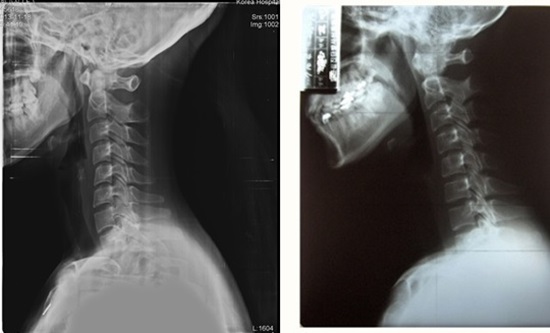

X-Ray를 찍어보면 디스크 간격도 좁아져 있습니다. 이런 목 디스크 질환은 목 척추뼈 사이 간격이 좁아져서 디스크가 붉어져 튀어나오거나 디스크의 수핵이 터져 나와 신경을 압박해서 나타나는 증상들 입니다. 목에서 나오는 신경이 목. 어깨의 근육과 팔, 손가락들을 담당하기 때문이죠. 그래서 신경이 눌리면 팔까지 저려오고 감각도 둔해지면서 팔의 힘도 약해지는 것입니다.